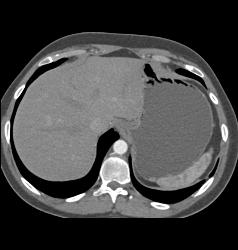

Infiltrative Carcinoma With Implants and Gastric Obstruction